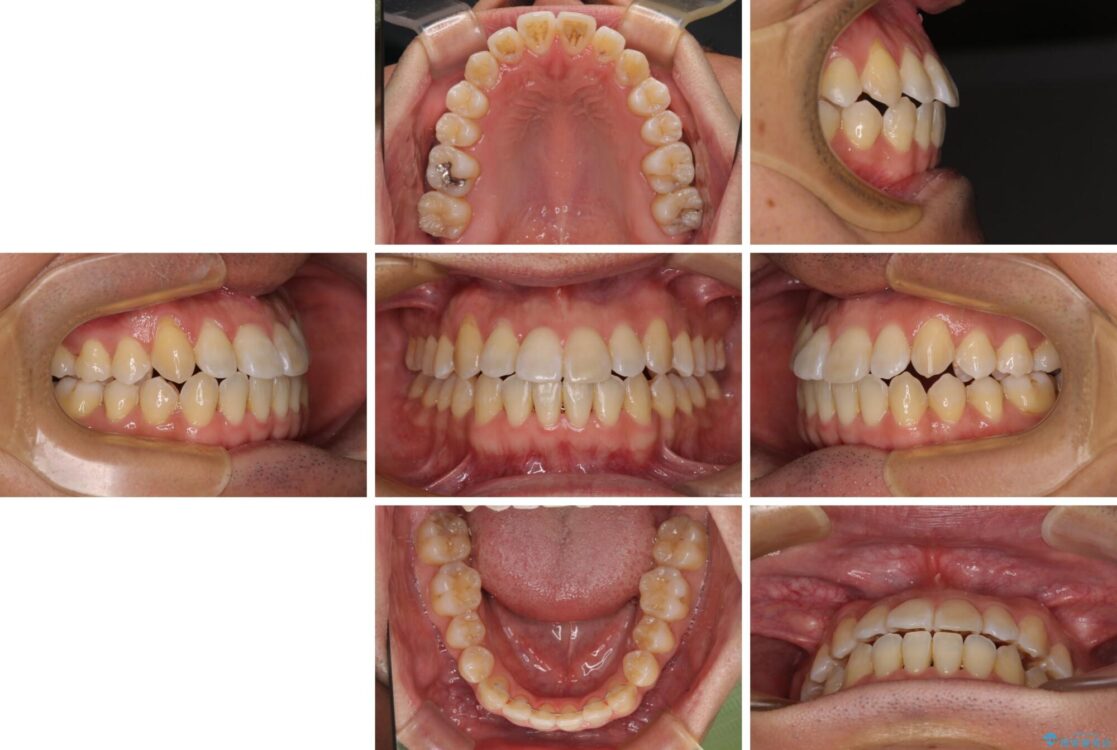

左右の八重歯が気になる ワイヤー装置での咬み合わせ改善

八重歯と前歯のデコボコを気にして来院された患者様です。

営業職であり、商談などで飲食をする機会が多いとのことで、インビザラインではなく、ワイヤー装置にて矯正治療を行うこととしました。

治療後について

舌の突出癖がなかなか改善されず、上下前歯部の接触が得られるまでに予定の倍ほどの期間がかかりました。

治療後

• 左右の八重歯が気になる ワイヤー装置での咬み合わせ改善 治療後画像